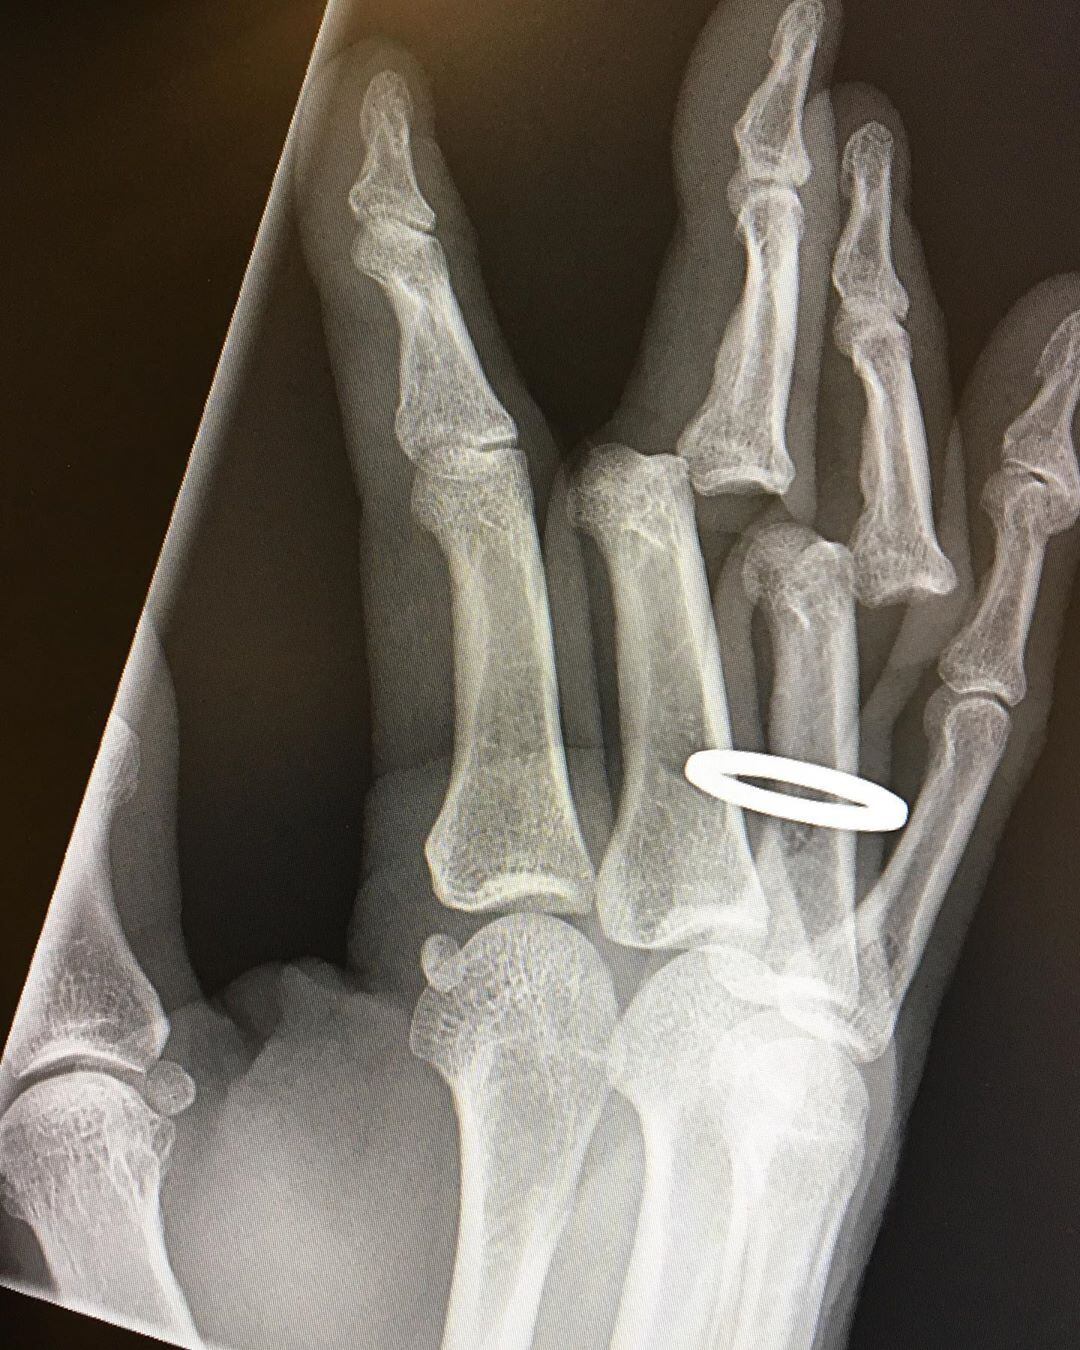

"Tuvieron que cortarme el anillo antes de devolver mis huesos a su posición vertical”, comentó Tony Hawk... qué gran tipo Tony Hawk

“Acabo de recibir mis radiografías. Tuvieron que cortarme el anillo antes de devolver mis huesos a su posición vertical”, escribió Tony Hawk agregando que “todavía están adoloridos, rígidos e hinchados, pero los puedo usar. Y todavía amo mi trabajo».